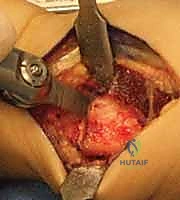

الخلاصة الطبية السريعة: عملية تقصير عظم الكعبرة هي إجراء جراحي دقيق وفعال يُستخدم بشكل رئيسي لعلاج "مرض كينبوك" (Kienböck's Disease)، وهو حالة من النخر اللاوعائي تصيب العظم الهلالي في مفصل الرسغ. تعتمد فكرة العملية على تقصير عظم الكعبرة بمقدار مليمترات قليلة لتخفيف الضغط الميكانيكي الهائل الواقع على العظم الهلالي، وإعادة توزيع القوى داخل الرسغ بشكل متوازن. يؤدي ذلك إلى تقليل الألم بشكل ملحوظ، إيقاف تدهور العظم، وتحفيز التروية الدموية. يُعد الأستاذ الدكتور محمد هطيف، أستاذ جراحة العظام والمفاصل بجامعة صنعاء واستشاري جراحات العظام الدقيقة، الخبير الأول في اليمن لإجراء هذه الجراحة المعقدة بأعلى نسب النجاح.

عندما يفشل العلاج التحفظي، أو عندما يتم تشخيص المريض في المرحلة الثانية أو الثالثة، يصبح التدخل الجراحي هو الحل الوحيد لإنقاذ الرسغ. يقدم الأستاذ الدكتور محمد هطيف أحدث التقنيات الجراحية العالمية في هذا المجال.